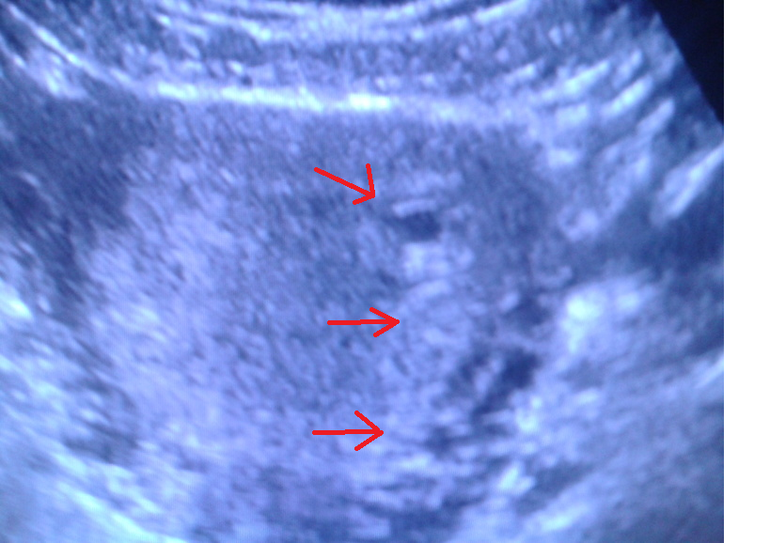

пришли с УЗИ) Узистка сказала что по животу делать узи смысла нет,ничего не будет видно...я говорю давайте,мол,попробуем....не хочу чтоб меня ковыряли лишний раз...в итоге она нашла ПОХОДУ ВОТ ЭТО ПЛОДНОЕ ЯЙЦО и КАЖЕТСЯ ЧТО ТО ЕЩЕ....что блин?)))кароче пойду еще в перинатальный через недели три...посмотреть что ж там еще то)))сказала что вагинальным датчиком можем разглядеть,но я отазалась

и фото чуть больше,вон в углу то самое "что то там еще" ...это не второй ли ребенок?)или они так далеко не цепляются друг от друга?кароч узнаю через три недели...

матка увеличена, 59х57х70(сказала, что большевата для такого срока)

миометрий не изменен, плодное яйцо 7мм)